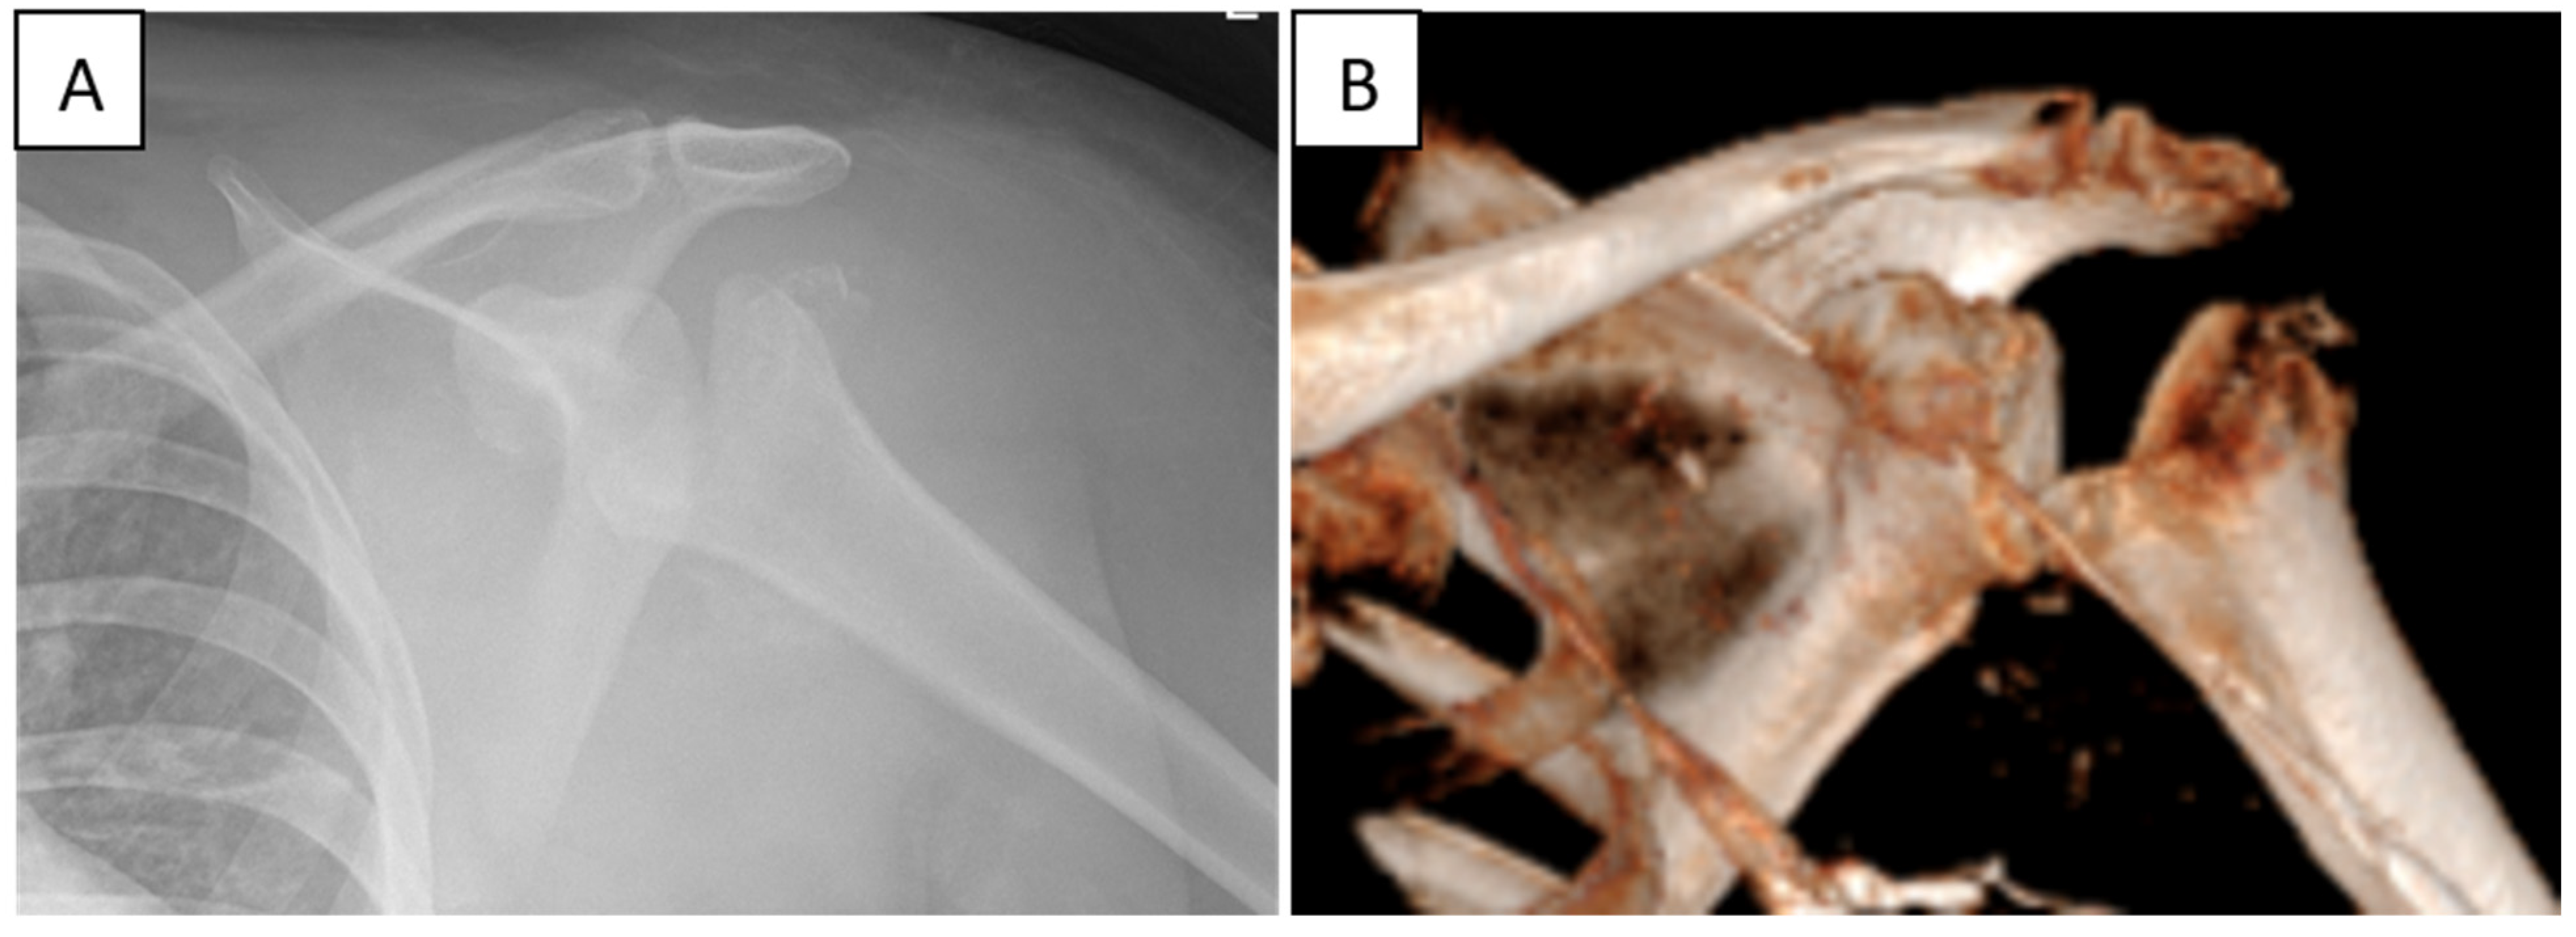

6.3. Charcot Joints and Neurogenic Arthropathy

9. Treatment Considerations in Charcot Shoulder

Back to Our Patient

- Orthopedic manifestations are frequent but under-recognized and may represent the earliest clinical signs. These include neurogenic arthropathy (Charcot joints)—most notably involving the shoulder—as well as pes cavus, scoliosis, gait disturbances, and unexplained limb weakness.

- Neuropathic shoulder arthropathy, though rare, can lead to progressive joint destruction due to impaired proprioception and pain perception. Early identification is crucial to prevent irreversible structural damage.